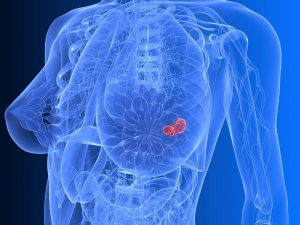

Sırt Ağrısı Kemik Erimesini İşaret Ediyor Olabilir